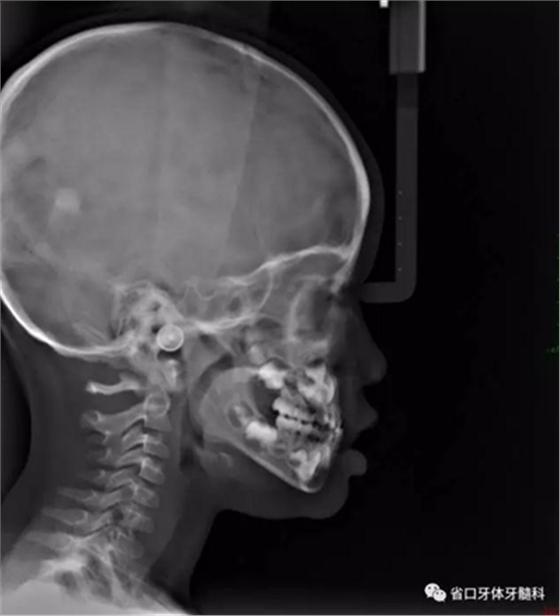

圖10 側(cè)位片

乳牙期前牙反合分為牙性、功能性和骨性

骨性前牙反合:由于上頜骨發(fā)育不足或者下頜發(fā)育過度導(dǎo)致前牙反合。

乳牙期前牙反合治療前先鑒別反合屬于牙性還是骨性反合,